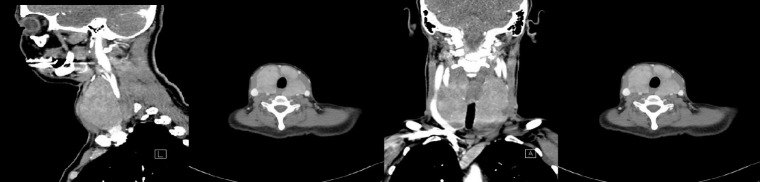

Hashimoto's thyroiditis (HT) is the most frequently diagnosed thyroid disorder worldwide, characterized by hypothyroidy and thyroid autoimmunity. The fibrous variant accounts for a small number of cases. A 48 years old woman, with 20-years history of Hashimoto thyroiditis presented for a large recent goiter with compressive symptoms, in hypothyroidic state and with very high thyroid antibodies antithyroglobulin and antithyroperoxidase. Ultrasound and fine needle aspiration biopsy showed an enlargement of the thyroid gland with nonhomogeneous structure and trachea shifting posteriorly, Bethesda III. CT scan showed similar aspect of the thyroid gland with compression on the trachea and the left common jugular vein. Surgery was performed due to suspicion of malignancy and compression symptoms. Thyroidectomy was uneventful, but the patient developed hypoparathyroid symptoms postoperatively that resolved with high dose calcium, magnesium and vitamin D supplementation. The pathology report was consistent of Hashimoto's thyroiditis fibrous variant. This case report presents a rare case of the fibrous variant of Hashimoto's thyroiditis that is rarely taken under consideration in the preoperative setting as diagnosis is hard to establish with the usual algorithm of imaging and FNA biopsy. The multidisciplinary management in pre-and postoperative approach and evaluation are of utmost importance for successful management of such case.